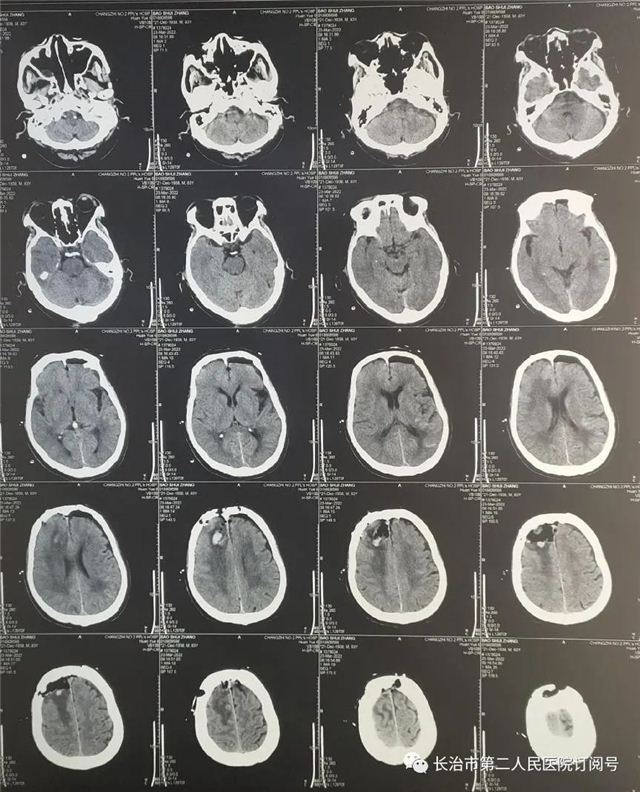

▲术后复查肿瘤全切,术野干净

▲术后复查:肿瘤全切、术野干净未见出血